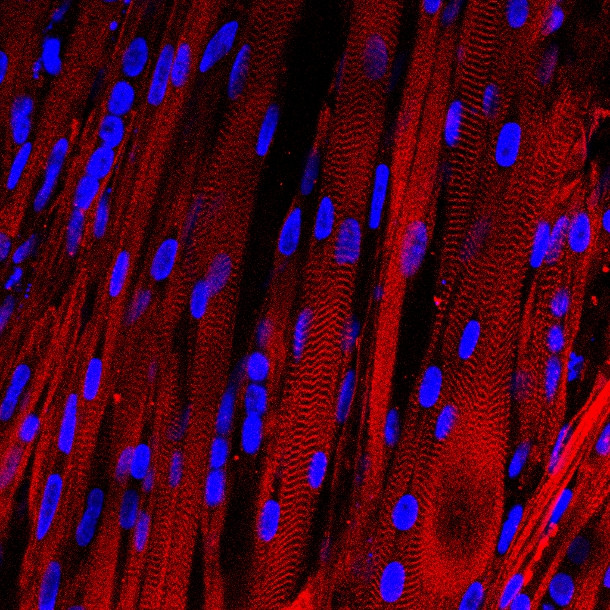

A microscopic view of lab-grown human muscle bundles stained to show patterns made by basic muscle units and their associated proteins (red), which are a hallmark of human muscle. (Credit: Duke University)

They expanded these “myogenic precursors” by more than a 1000-fold, and then put them into a supportive, 3D scaffolding (support structure) filled with a nourishing gel that allowed them to form aligned and functioning muscle fibers.

“We have a lot of experience making bioartifical muscles from animal cells in the laboratory, and it still took us a year of adjusting variables like cell and gel density and optimizing the culture matrix and media to make this work with human muscle cells,” said Madden.

She found that the muscles robustly contracted in response to electrical stimuli — a first for human muscle grown in a laboratory. She also showed that the signaling pathways allowing nerves to activate the muscle were intact and functional.

Existing in vitro models of human skeletal muscle cannot recapitulate the organization and function of native muscle, limiting their use in physiological and pharmacological studies. Here, we demonstrate engineering of electrically and chemically responsive, contractile human muscle tissues (‘myobundles’) using primary myogenic cells. These biomimetic constructs exhibit aligned architecture, multinucleated and striated myofibers, and a Pax7+ cell pool. They contract spontaneously and respond to electrical stimuli with twitch and tetanic contractions. Positive correlation between contractile force and GCaMP6-reported calcium responses enables non-invasive tracking of myobundle function and drug response. During culture, myobundles maintain functional acetylcholine receptors and structurally and functionally mature, evidenced by increased myofiber diameter and improved calcium handling and contractile strength. In response to diversely acting drugs, myobundles undergo dose-dependent hypertrophy or toxic myopathy similar to clinical outcomes. Human myobundles provide an enabling platform for predictive drug and toxicology screening and development of novel therapeutics for muscle-related disorders.